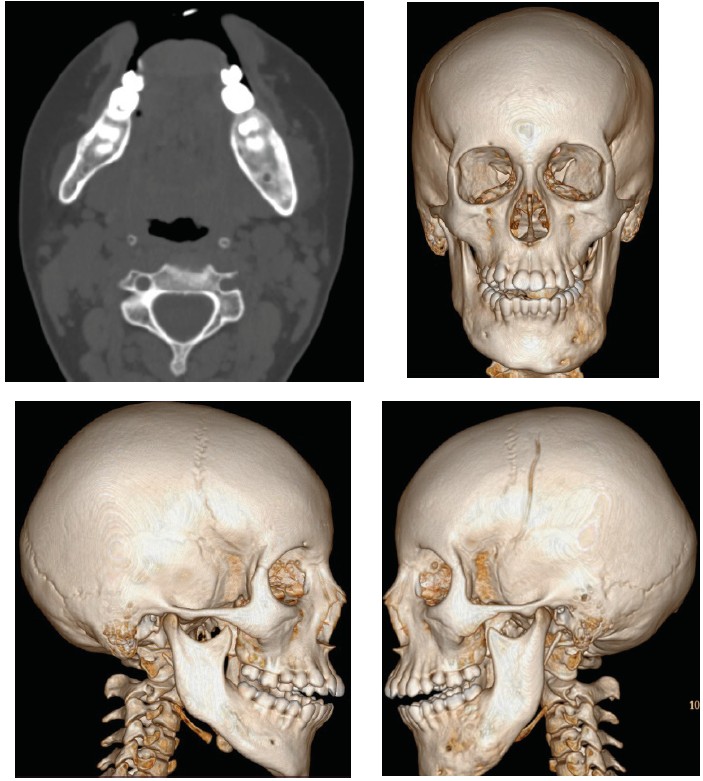

Monitoring the patient’s condition in the year following reveals that the regions of bone destruction were filled, despite the retention of the irregular morphology of the external contour of the mandible. Notably, the child remained pain free throughout this period (Figure 4).

Fig. 4. MSCT scan in May 2023 showing the recovering process of the mandible with the remaining of uneven contour of the left half of the mandible

Similarly, a MSCT scan conducted in June 2024, one year later, revealed evidence of bone regeneration, with the external contour of the mandible returning to its typical dimensions and morphology (Figure 5).

Fig. 5. MSCT scan in June 2024 exhibiting the evidence of bone regeneration and positive dynamic of the treatment protocol. It can be clearly seen the positive effect of adding Denosumab to the treatment protocol in keeping the good outcome of the operation